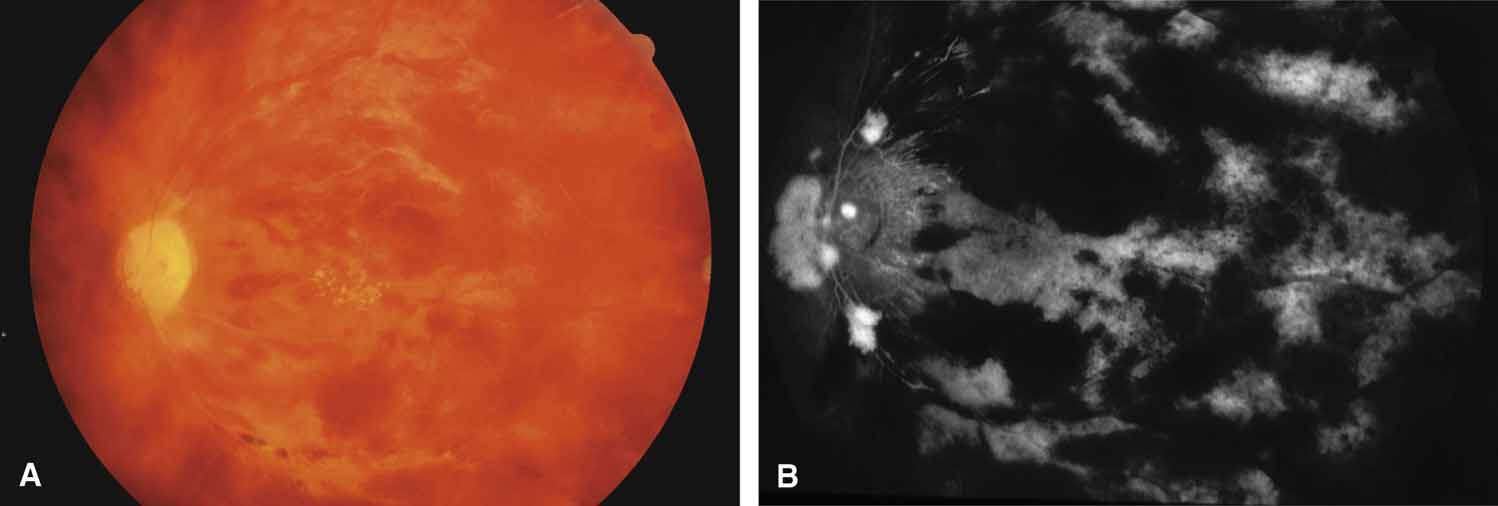

Postoperative Panretinal Photocoagulation

Most of the mild, asymptomatic, and transient pressure elevations noted immediately after panretinal photocoagulation occur by unknown mechanisms in the presence of an open angle.92 Occasionally, heat-induced choroidal congestion, choroidal vascular permeability, and choroidal vascular obstruction may, as discussed previously, result in ciliary body rotation and closure of the peripheral angle (Fig. 18). Usually the narrow or closed angles resolve within several days, and thus far no severe visual complications have been reported. Choroidal congestion/effusion occurs frequently but is usually not clinically significant or recognized. Limiting the number of laser burns and the amount of retinal area treated can prevent this problem from occurring.93 Dividing panretinal photocoagulation treatments into two or more sessions several weeks apart is advisable when possible. Photocoagulative pressure elevations usually respond to cycloplegia, aqueous suppressants (acetazolamide and timolol), and osmotics.94

Fig. 18 Panretinal photocoagulation with elevated intraocular pressure. A. Elevated intraocular pressure was noted in the first few hours following scatter laser photocoagulation of the proliferative diabetic retinopathy. B. Four days later the same patient noted blurred vision and was found to have peripheral choroidal detachments, a closed peripheral angle, and intraocular pressure of 35 mm Hg. Treatment with cycloplegics, topical corticosteroids, timolol maleate, and acetazolamide produced a rapid drop in pressure. The choroidal detachments resolved completely in 10 days.